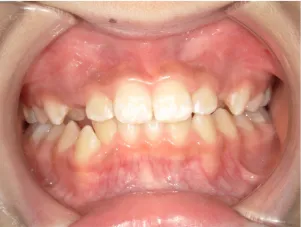

治療前①小5:生え変わり後期のため顔の成長を促進させる目的で拡大装置(アーチ形態の修正)と上顎前歯をそろえることを先行し、できるだけ非抜歯治療で進める予定を提案しました

| はじめのご相談 | 凸凹を治したい、治療方法を知りたい。 |

| カウンセリング・診断結果 | 治療方法は精密検査、分析をして検討することをご理解いただき、矯正治療で抜歯をするかしないかの違いについて説明し治療を希望されたので精密検査を行いました。 精検の結果、顔立ちは下顎が後退したタイプの出っ歯(下顎後退型上顎前突)でV-shaped arch(歯列が狭い)、凸凹、八重歯になっていて、機能的にはべろのポジションが悪い低位舌があります。 口元は問題ありません。 |

| 行ったご提案・診断内容 | 生え変わりが終わってなくマルチブラケット法による咬合治療には早い時期のため、顔立ちの成長を促す目的で歯列弓(アーチ)の拡大と前歯を並べながら永久歯が生えるのを待ち、咬合治療開始時に再診断で抜歯、非抜歯を最終検討する提案をしました。 再診断時(写真②)、歯列の拡大と上顎前歯の並べ替えはされていましたが八重歯となったため抜歯、非抜歯を検討しました。 口元は特に問題がなく非抜歯で八重歯を改善するためのスペースを作ることが可能なため非抜歯治療を提案しました。 治療は、 ・拡大および上顎左右6を遠心移動させてスペースを作る 予定装置 |